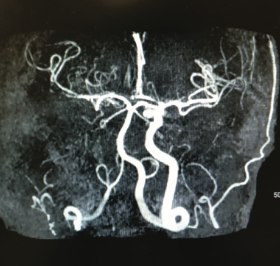

This photo essay includes a collection of case reports involving conditions relating to cardiometabolic disease.